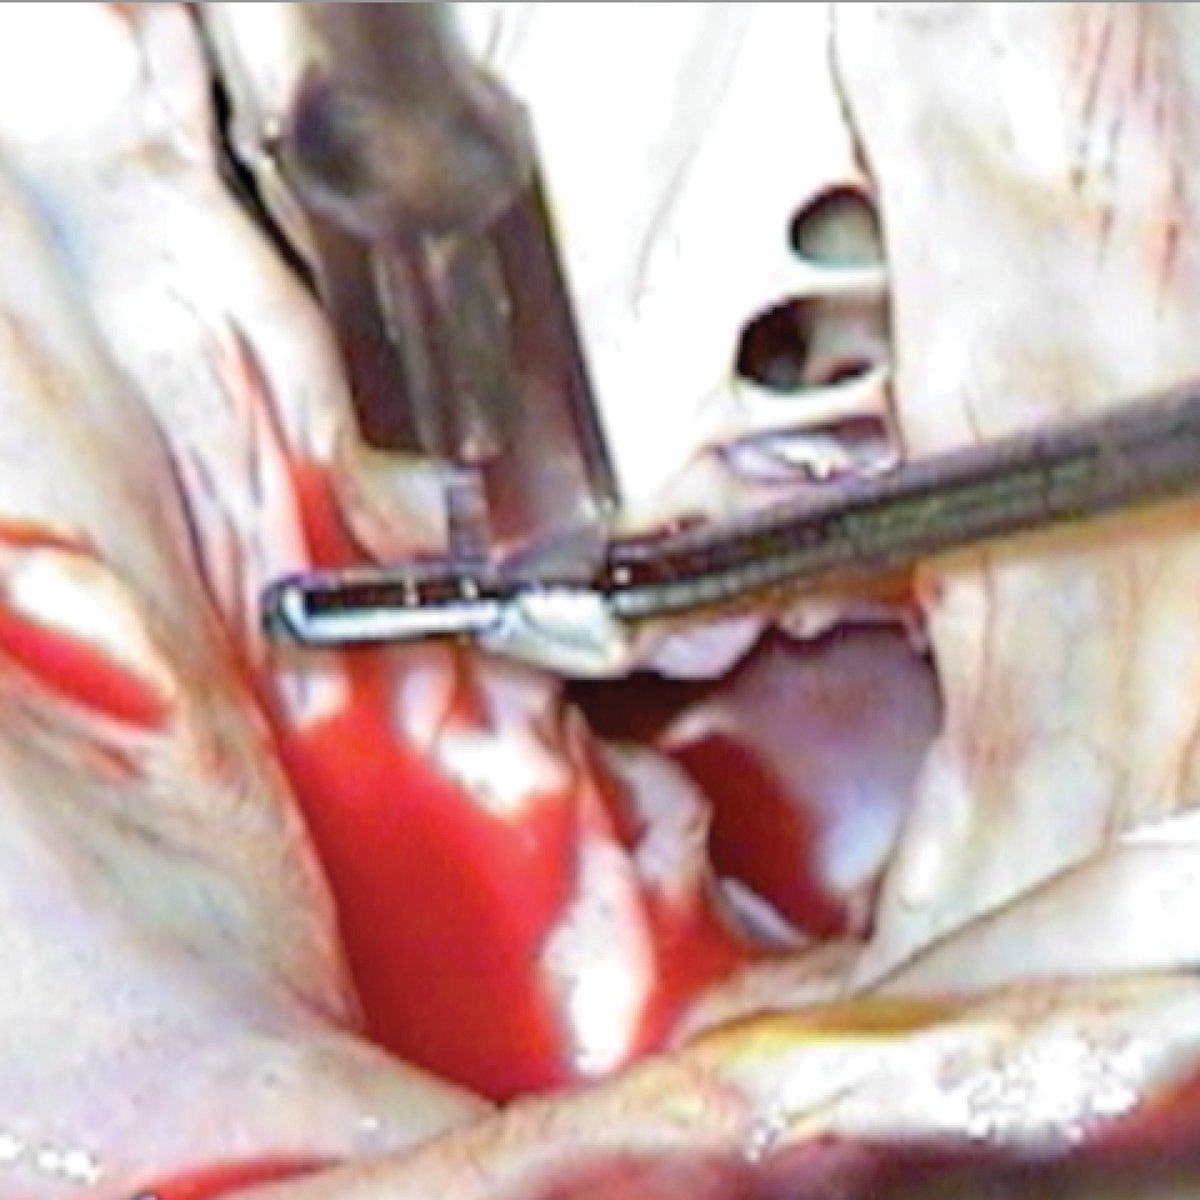

SURGEON TESTIMONIAL: “The Drake Hook is an important tool for subvalvular mitral repair. The cutting groove facilitates safe commissurotomy and chord lysis.” - Daniel H. Drake, MD #ThompsonRetractor

ThompsonRetract's tweet image. SURGEON TESTIMONIAL: “The Drake Hook is an important tool for subvalvular mitral repair. The cutting groove facilitates safe commissurotomy and chord lysis.” - Daniel H. Drake, MD #ThompsonRetractor